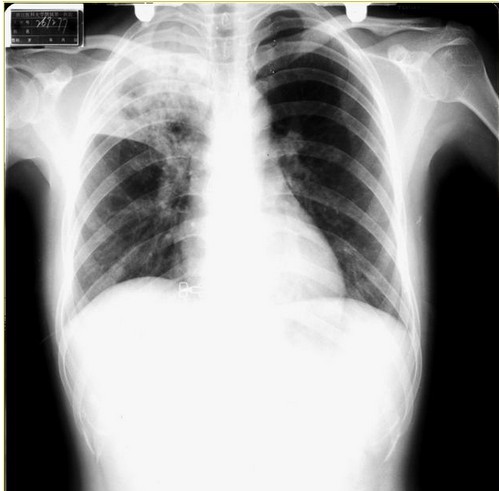

胸片

胸片经常用于检查胸廓(包括肋骨,胸椎,软组织等),胸腔,肺组织,纵隔,心脏等等的疾病。如肺炎,肿瘤,骨折,气胸,肺心病,心脏病。

胸片是临床应用最为广泛的检查之一。简便便宜。能筛查出很多疾病,比如肿瘤性疾病,很多老年人由于咳嗽,到医院照胸片检查,才发现有可疑肿瘤,便可进一步胸部CT检查以便进一步确定诊断。慢性阻塞性肺疾病病人突然出现胸痛,可能是气胸,此时体格检查一般可作出诊断,而快速胸片也可确定诊断。高血压性心脏病患者,胸片可见心脏增大。车祸病人,可能导致肋骨骨折,此时胸片可确定诊断,必要时还需要胸部CT进一步明确诊断。年轻人淋雨着凉后出现咳嗽、胸痛、咳痰等症状,怀疑肺炎,胸片可见大片高密度影,可确定为肺炎。长期慢性咳嗽的瘦弱女子,可能有肺结核,此时胸片也可提供证据,只要是肺尖有病灶。